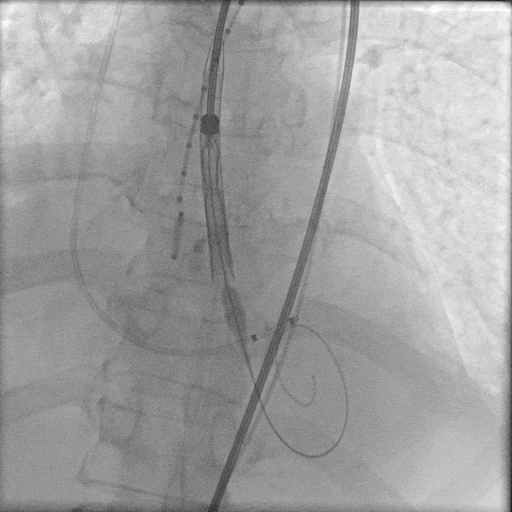

TaurusElite 输送器轻松过弓、跨瓣,LAO 11° CRA 15°投照角度下,第一次定位。

TaurusElite轻松过弓

第一次定位

第一次释放后,造影评估深度偏深,随即完全回收。

第一次释放

第一次回收